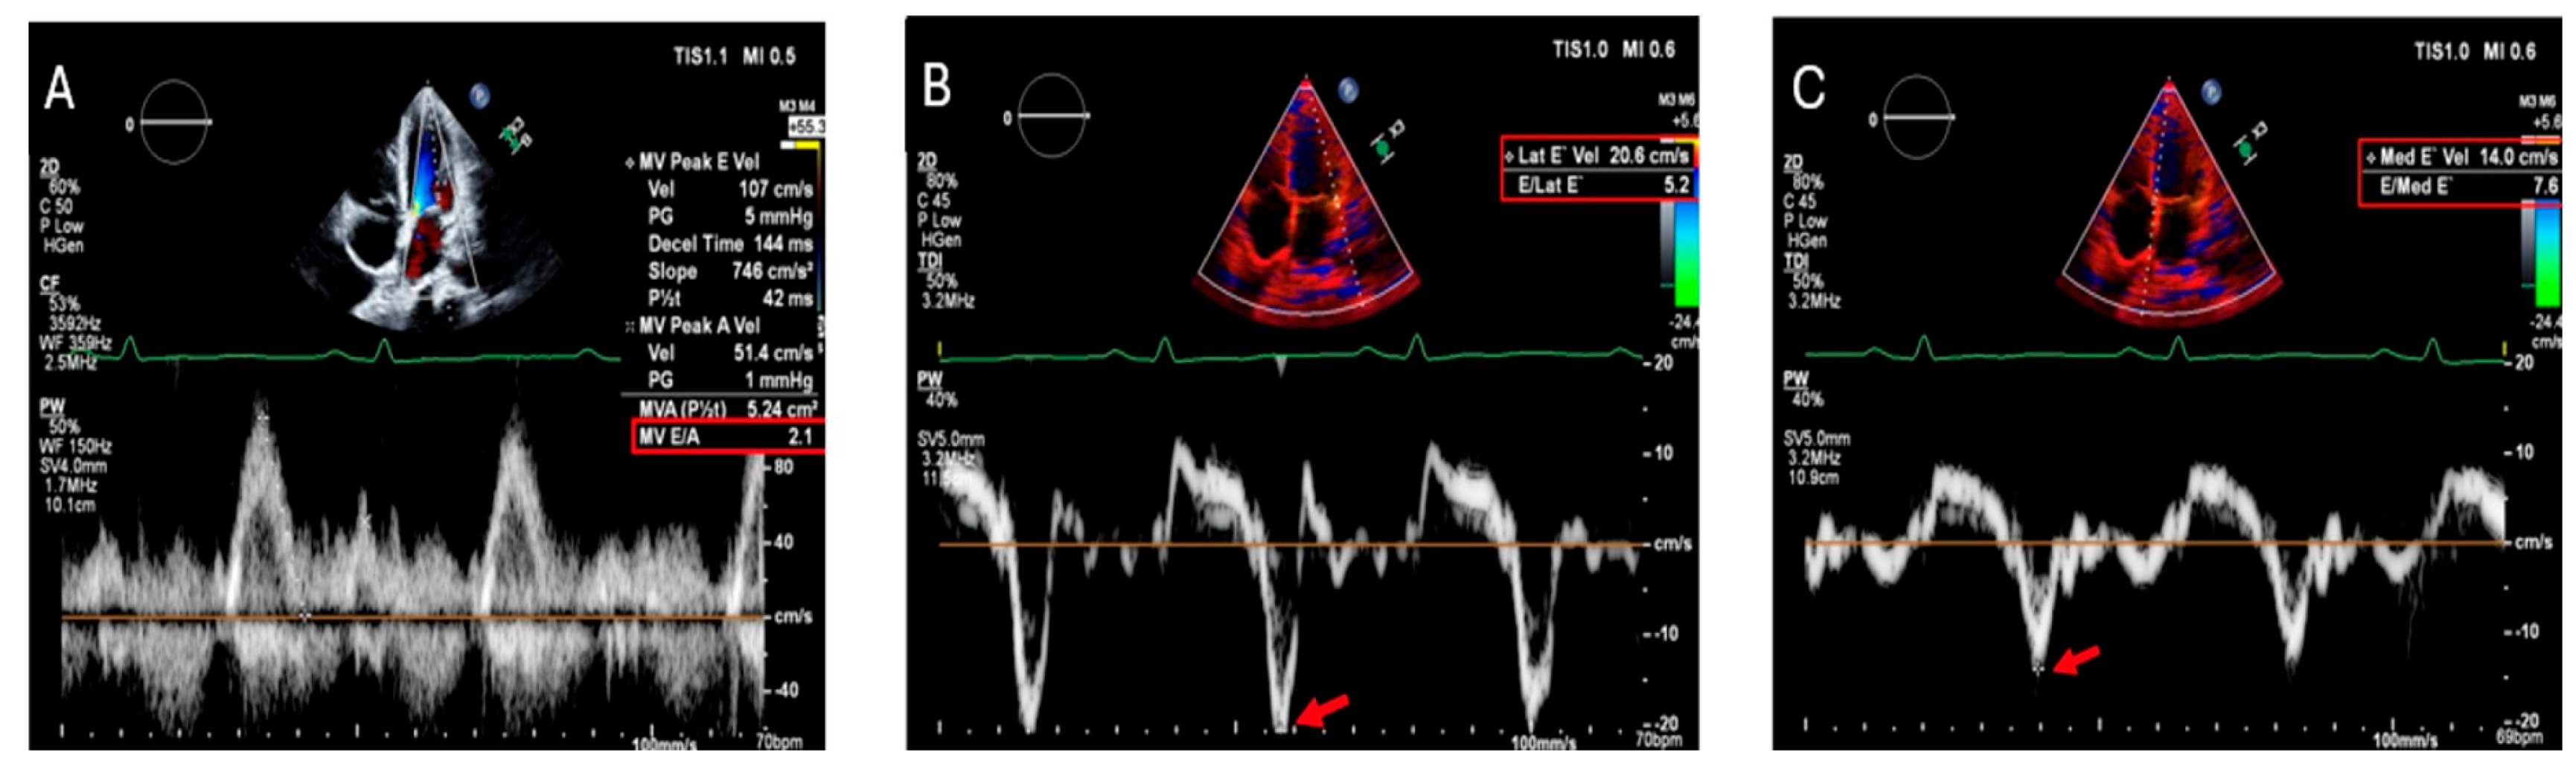

- Świątczak, M.; Rozwadowska, K.; Sikorska, K.; Młodziński, K.; Świątczak, A.; Raczak, G.; Daniłowicz-Szymanowicz, L. The Potential Impact of Hereditary Hemochromatosis on the Heart Considering the Disease Stage and Patient Age—The Role of Echocardiography. Front. Cardiovasc. Med. 2023, 10, 1202961. [Google Scholar] [CrossRef]

- Palka, P.; Macdonald, G.; Lange, A.; Burstow, D.J. The Role of Doppler Left Ventricular Filling Indexes and Doppler Tissue Echocardiography in the Assessment of Cardiac Involvement in Hereditary Hemochromatosis. J. Am. Soc. Echocardiogr. 2002, 15, 884–890. [Google Scholar] [CrossRef]

- Aypar, E.; Alehan, D.; Hazirolan, T.; Gümrük, F. The Efficacy of Tissue Doppler Imaging in Predicting Myocardial Iron Load in Patients with Beta-Thalassemia Major: Correlation with T2* Cardiovascular Magnetic Resonance. Int. J. Cardiovasc. Imaging 2010, 26, 413–421. [Google Scholar] [CrossRef]